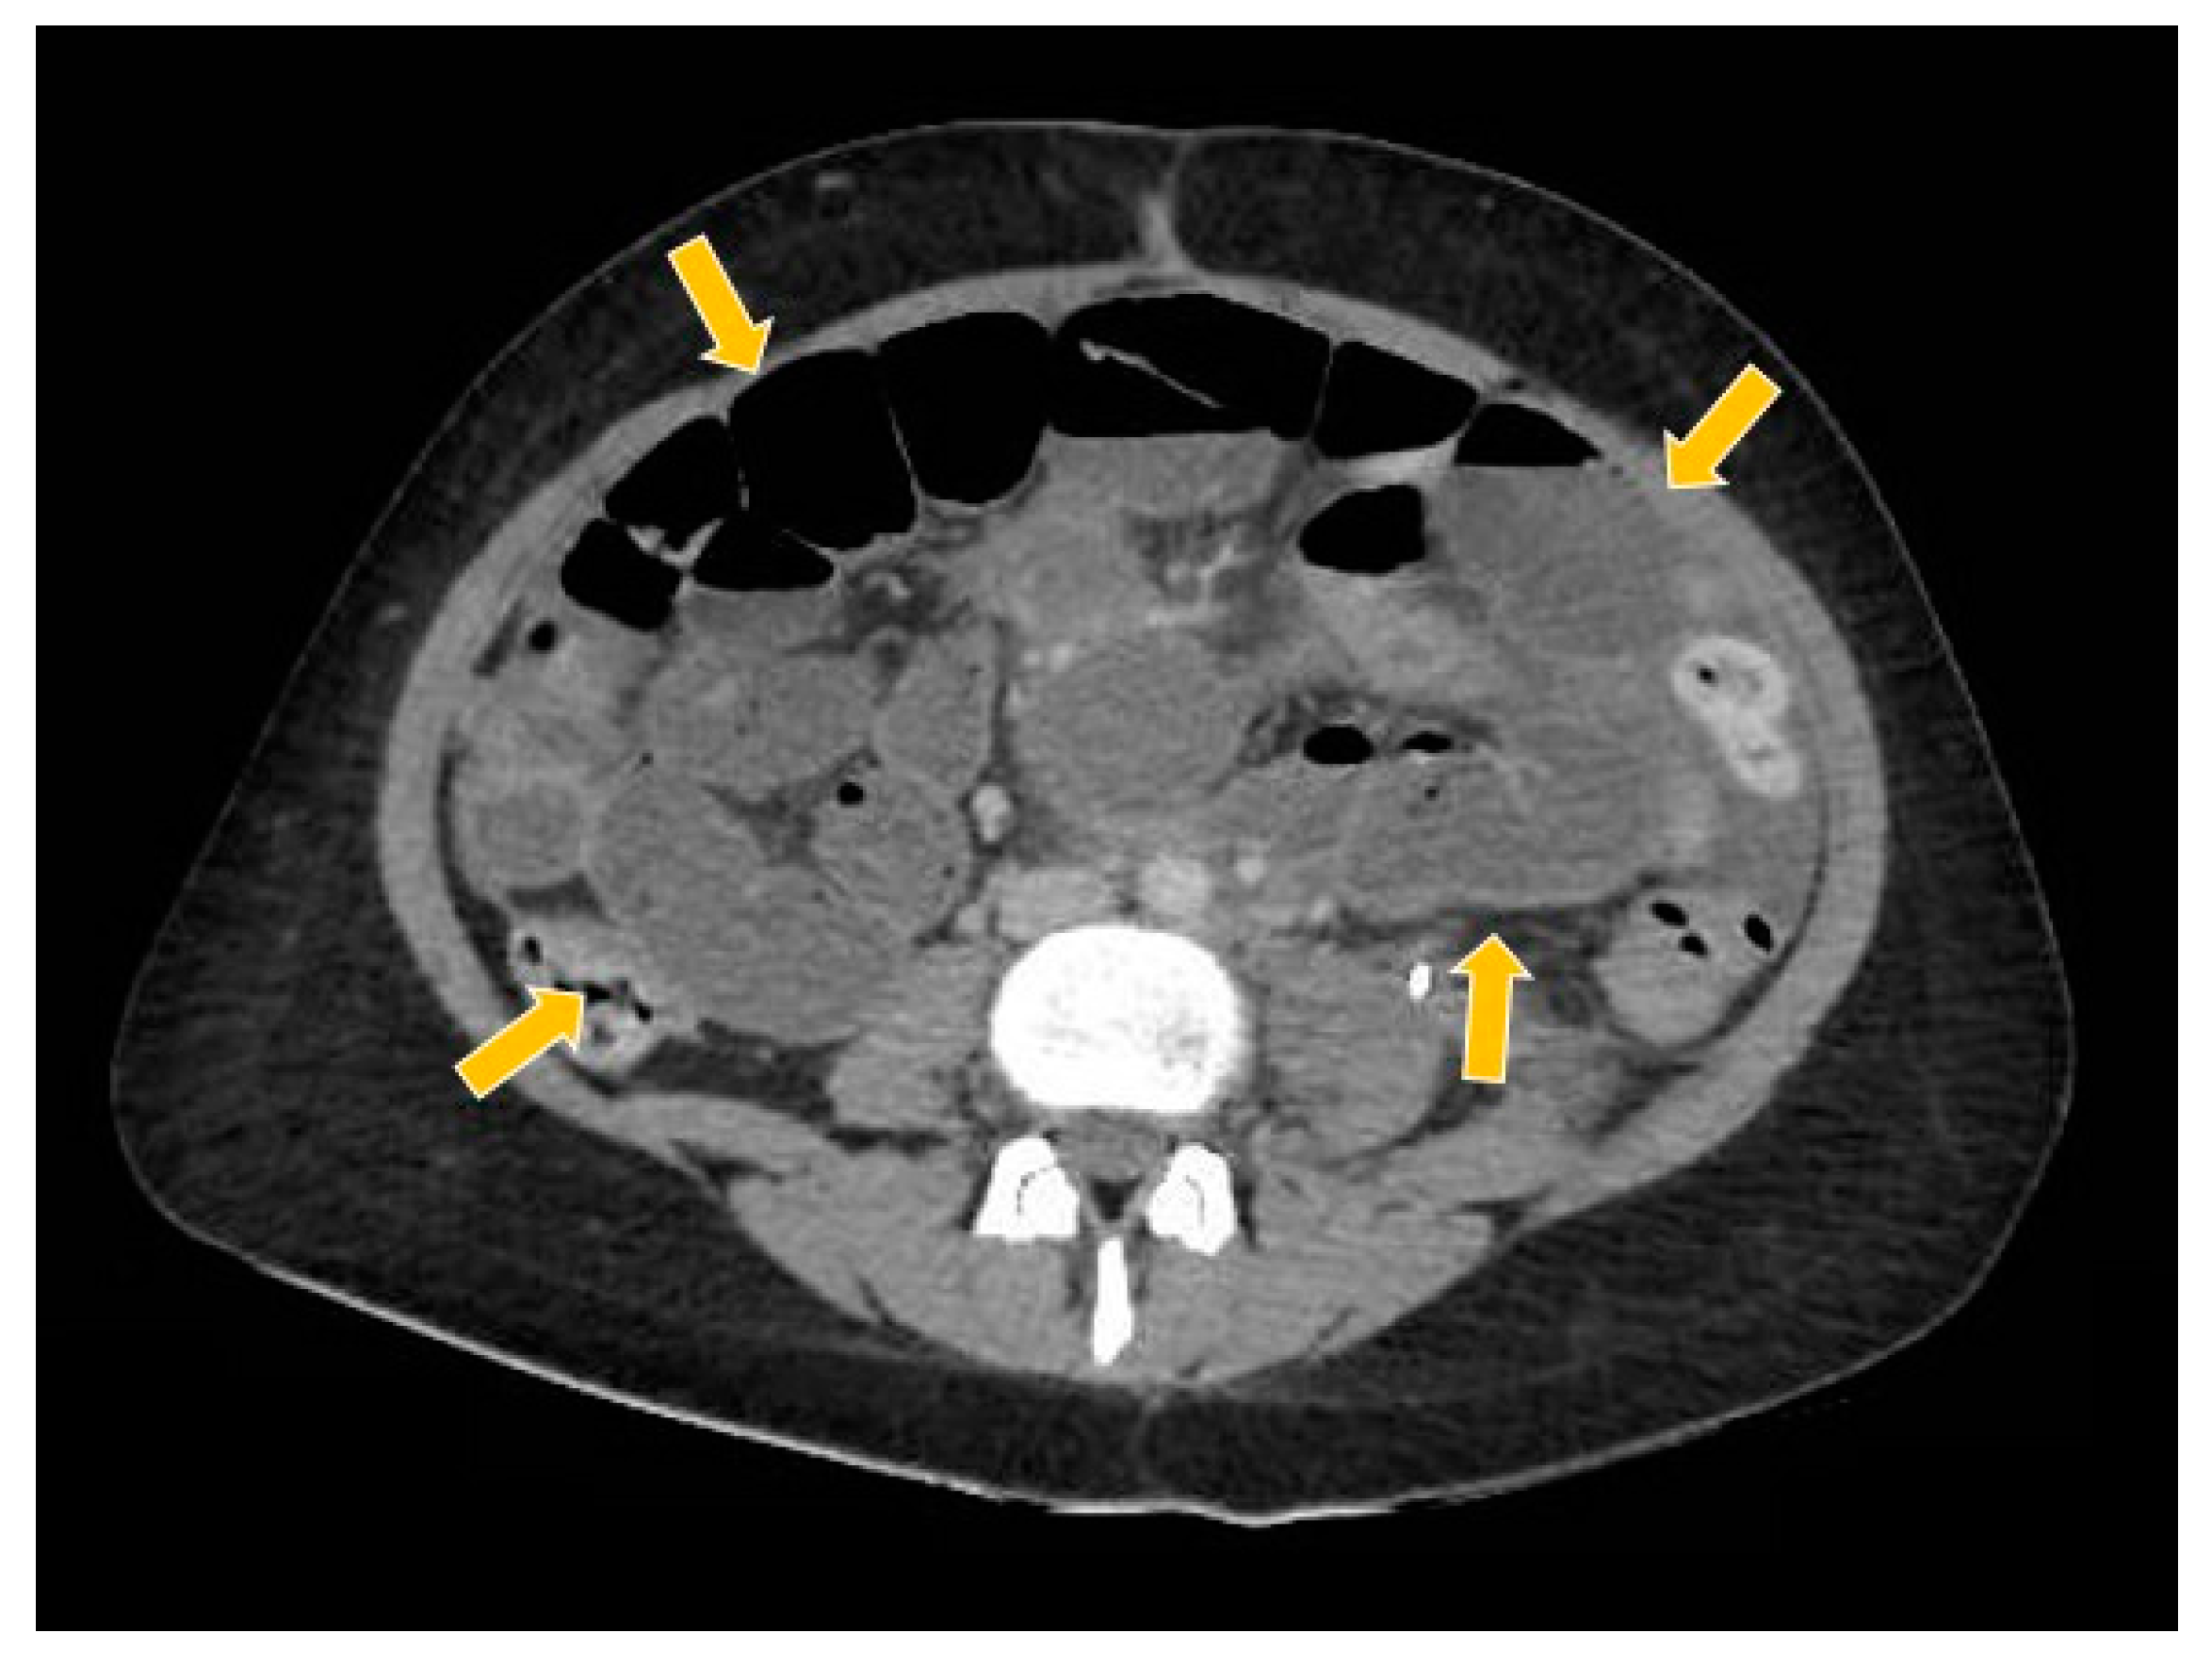

Figure 10.

The computed tomography study in the portal phase showing the dilation of slender loops (yellow arrows) by distal extrinsic compression (new pelvic lesion).